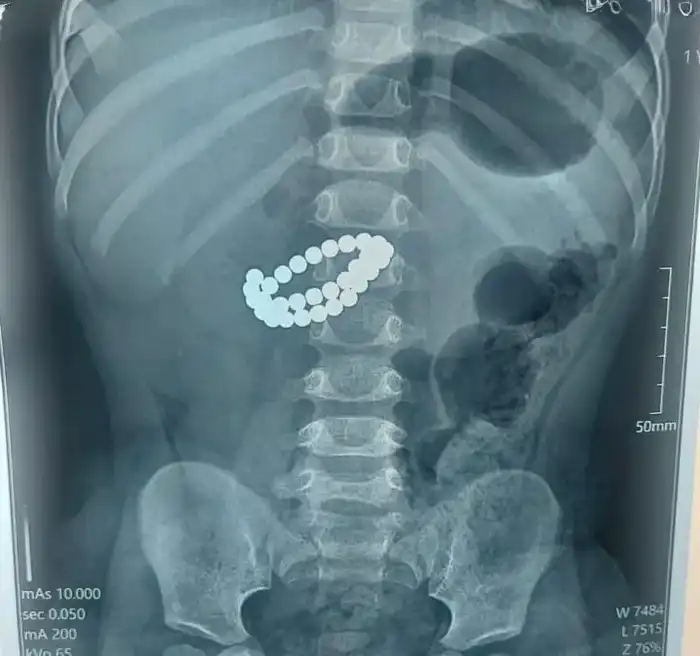

Экстренная операция в Алматы: хирурги спасли ребенка после проглатывания 31 магнита

В Алматы произошел тревожный инцидент, когда 1,9-летний ребенок был госпитализирован в критическом состоянии после проглатывания 31 магнита. По информации управления общественного здравоохранения города, у малыша были обнаружены серьезные повреждения: множественные перфорации тонкой кишки и диффузный каловый перитонит. Врачи отметили, что единственным шансом на спасение жизни ребенка стало срочное хирургическое вмешательство.

Экстренная операция, проведенная в Центре детской неотложной медицинской помощи Алматы, включала срединную лапаротомию с ревизией органов брюшной полости, где хирурги извлекли магниты и зашили перфорации. Хирург Аскар Ризванов подчеркнул, что опасность магнитов заключается в их способности притягиваться друг к другу внутри кишечника, что приводит к зажиманию стенок кишки, нарушению кровообращения и, в конечном итоге, некрозу тканей. В результате таких процессов может развиться перитонит всего за несколько часов.